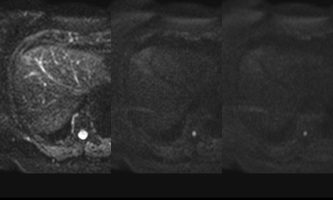

El estudio se complemento con resonancia magnética, donde se demostró la presencia de múltiples imágenes focales hepáticas confluentes con disminución de la señal en secuencias fuera de fase, no mostrando alteración de la señal en secuencias potenciadas en T2, sin signos de restricción al pulso difusión ni refuerzos anómalos luego de la administración de contraste endovenoso, estos hallazgos confirman la sospecha de esteatosis focal multinodular (fig. 5, 6 y 7).

En estos casos se recomienda realizar RM para confirmar la presencia de grasa en las “lesiones” identificadas y descartar otras etiologías, demostrando disminución de la señal en secuencias fuera de fase, sin alteración del pulso difusión (fig. 12 y 13).